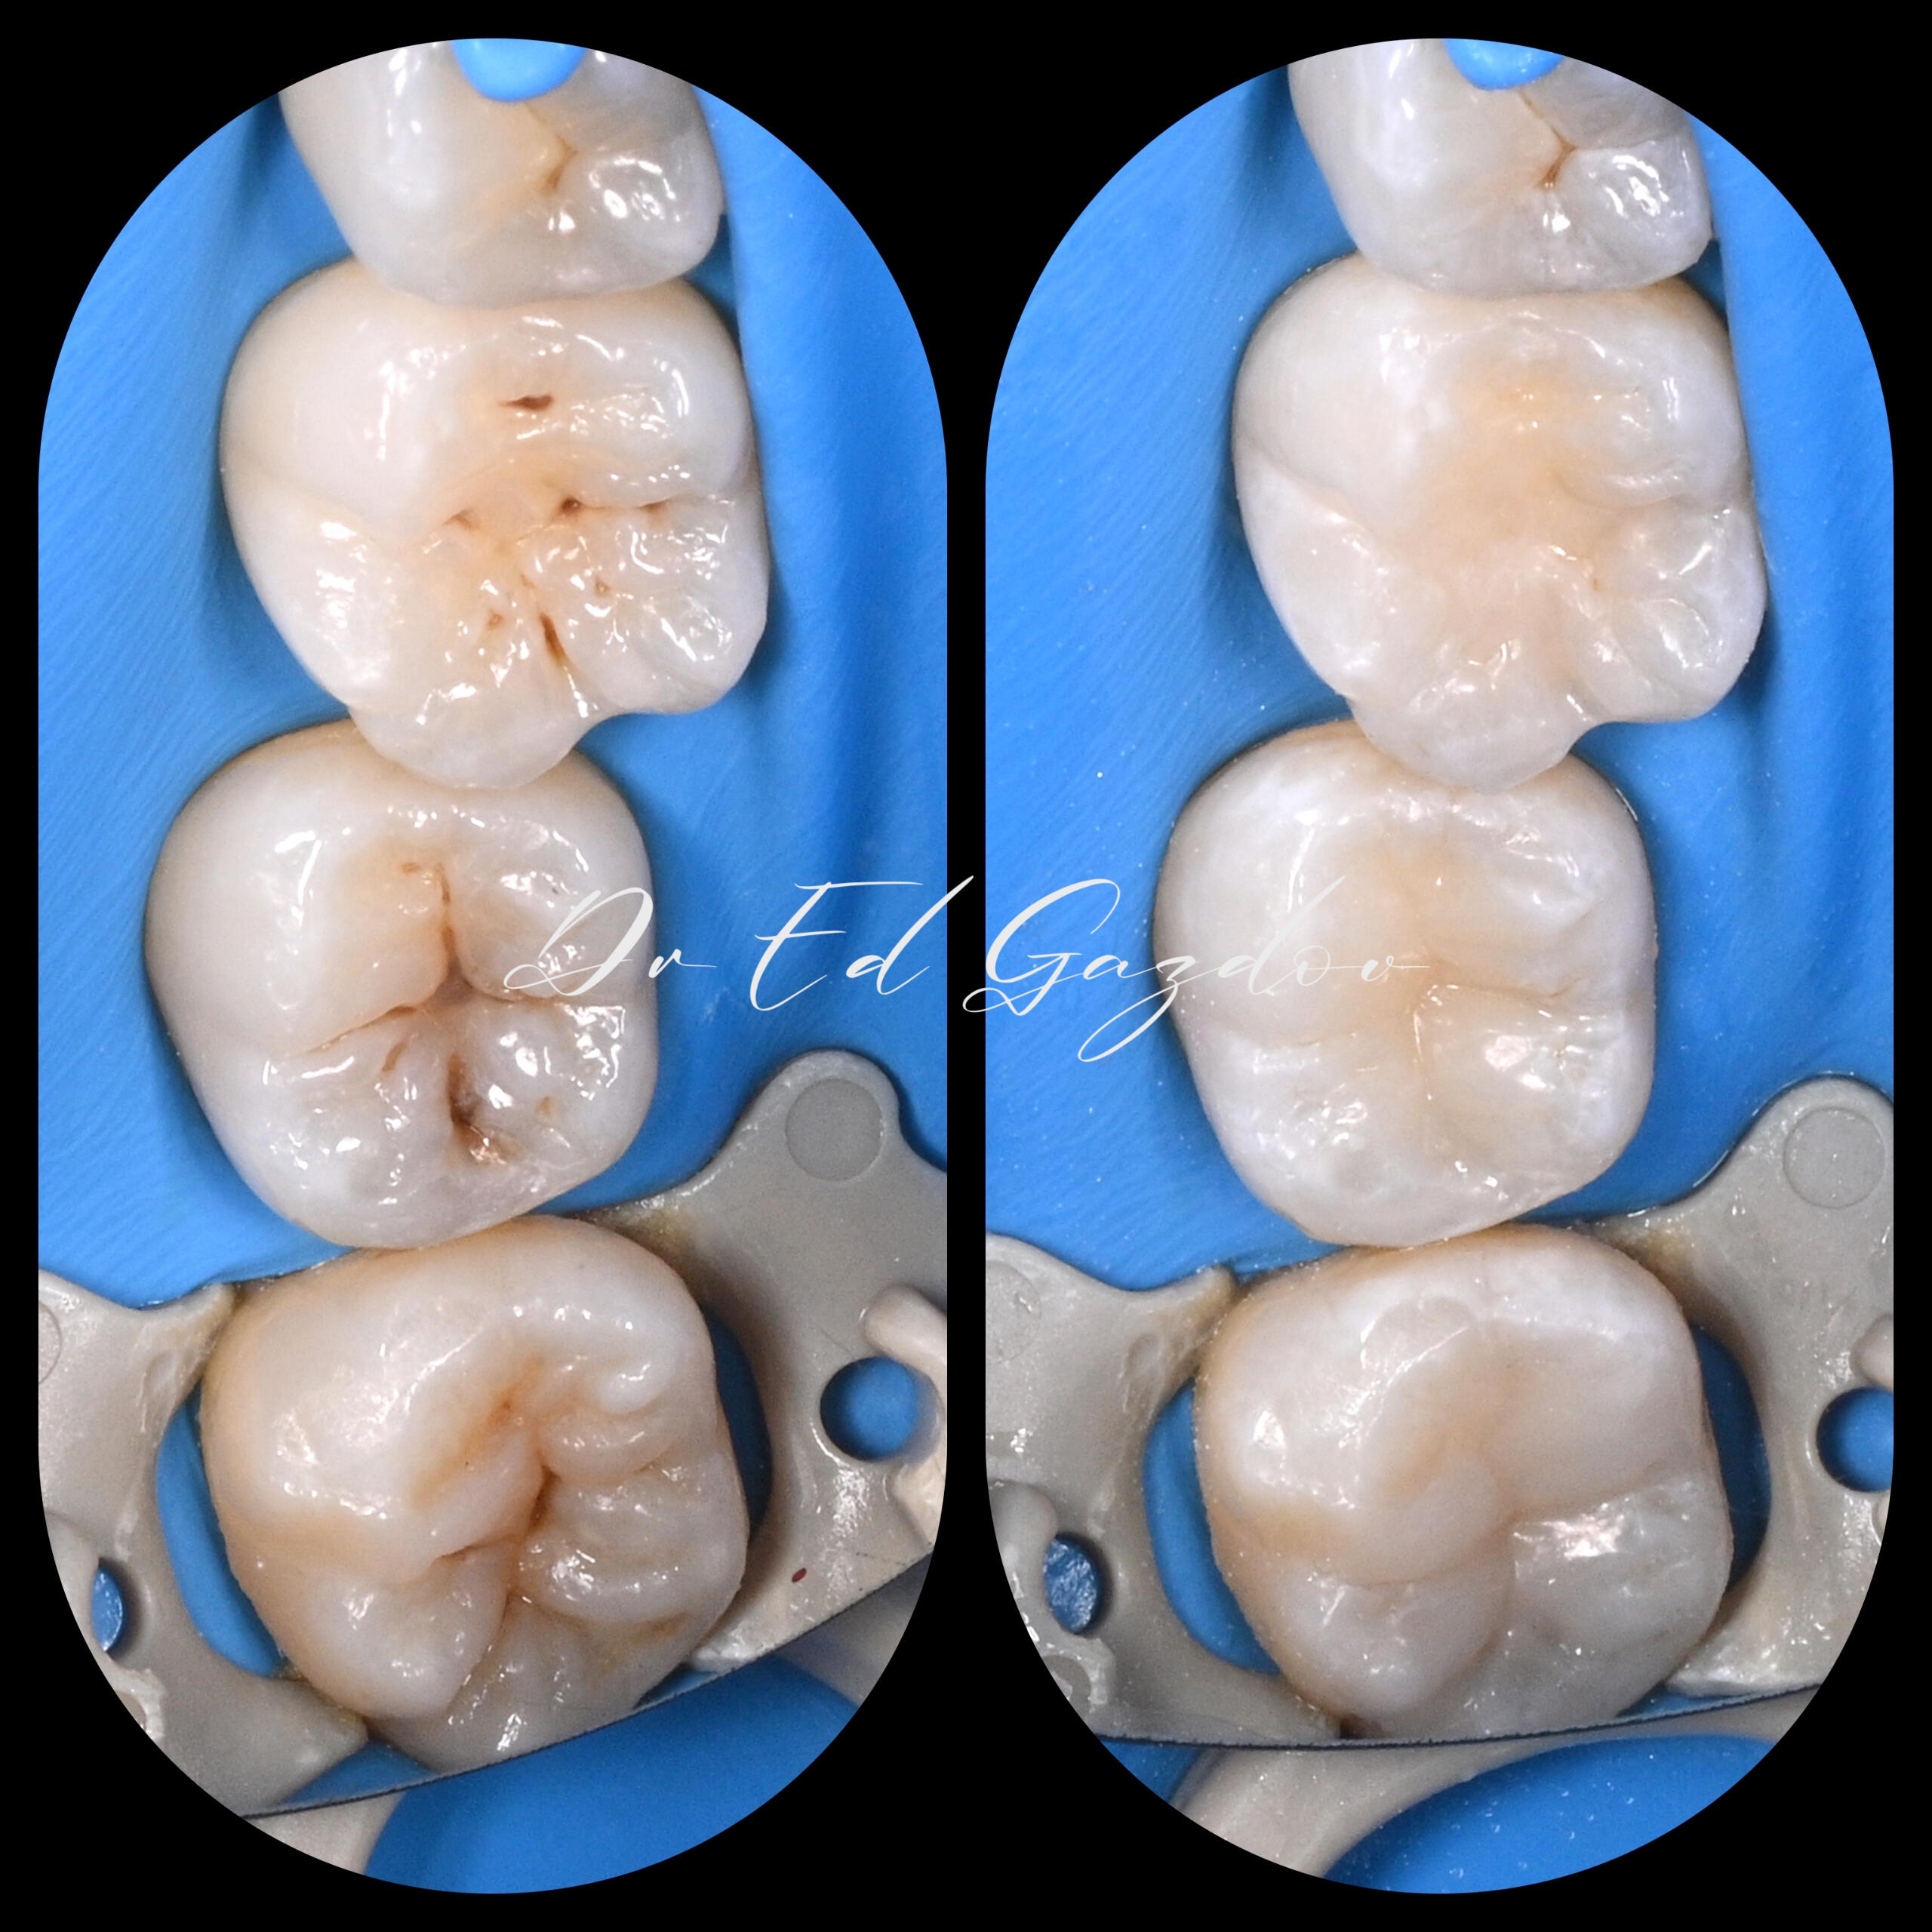

ПРЕДИ И СЛЕД

🦷 Истински резултати. Истински хора.Всяка усмивка, която виждате тук, е реален случай, лекуван лично от Д-р Едуард Газдов – от първия преглед до последната фина настройка.Работим с внимание към детайла, с модерни и щадящи методи, и с лично отношение към всеки пациент. Независимо дали става дума за пълна трансформация, единичен зъб или сложно релечение – подходът ни е прецизен, внимателен и изцяло съобразен с нуждите Ви.⸻🛠️ Какво предлагаме:

• Директни фотополимерни възстановявания – бързо и щадящо решение при отчупвания и леки корекции

• CEREC корони и инлеи, изработени и поставени на място, в рамките на часове